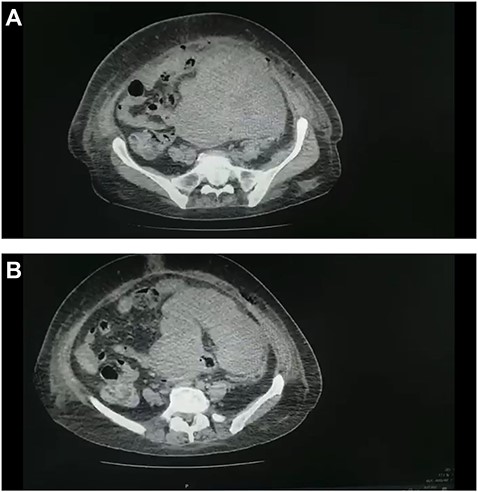

(A and B) CT scan of the abdomen and pelvis demonstrated a large pelvic mass adherent to the sigmoid colon and compressing its surrounding structures.

Tumour arising from the sigmoid colon, adherent to the small bowel and measured 12 × 13 × 16 cm.

Abdominal ultrasound revealed a bulky hypoechoic pelvic mass with ill-defined borders. Computed tomography (CT) scan of abdomen and pelvis established a large pelvic mass adherent to the sigmoid colon and compressing its surrounding organs measuring approximately 10 × 11 × 13 cm. (Fig. 1A and B). Initial management included intravenous fluid resuscitation, analgesics and prophylactic antibiotics.